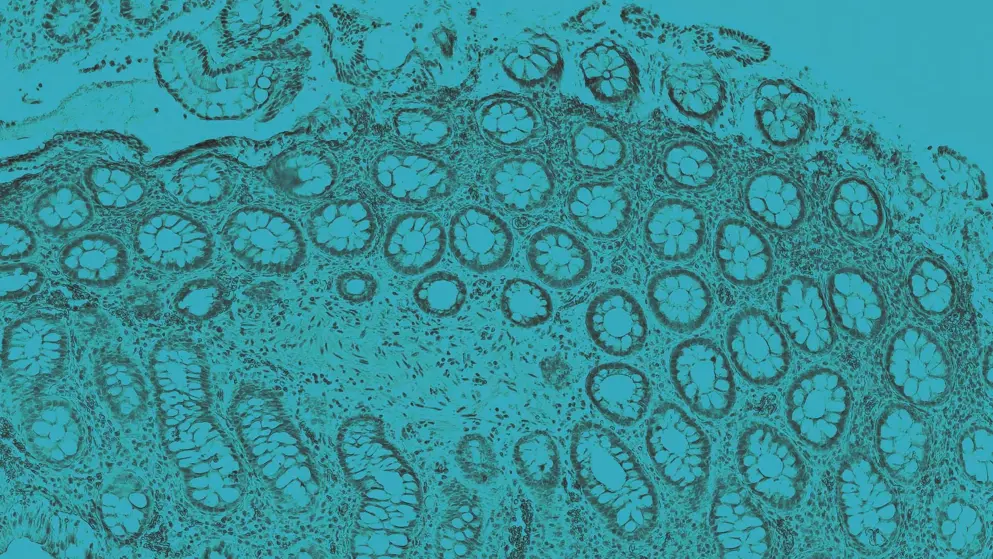

Ulcerative colitis (UC) is a chronic inflammatory bowel disorder of the colon with a relapsing and remitting course1,2. People with UC frequently present with mucus-like diarrhoea containing blood, as well as abdominal pain and rectal urgency, which are characteristic symptoms of this disorder3.